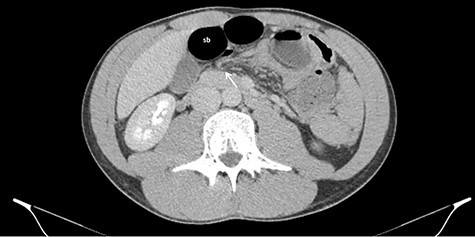

Axial CT images of dilated small bowel (sb) with the respective mesentery converging to the hernia defect (white arrow) in the gastrohepatic ligament.